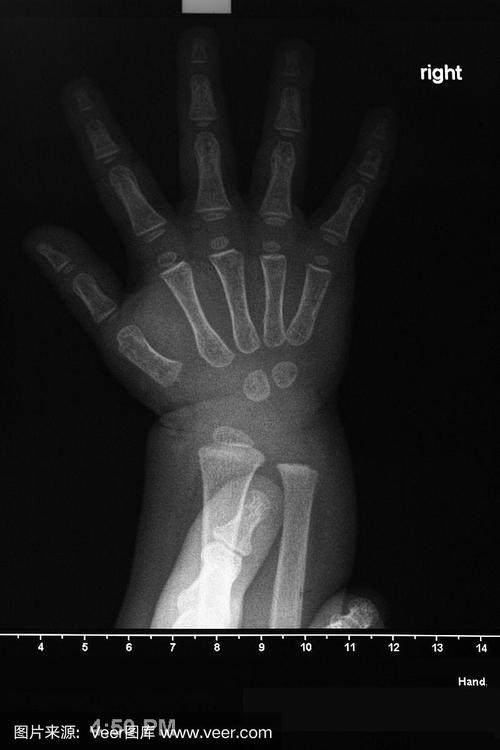

- 检查骨骼:查看是否有骨折(尤其是难产或产伤的新生儿)、骨骼发育问题。